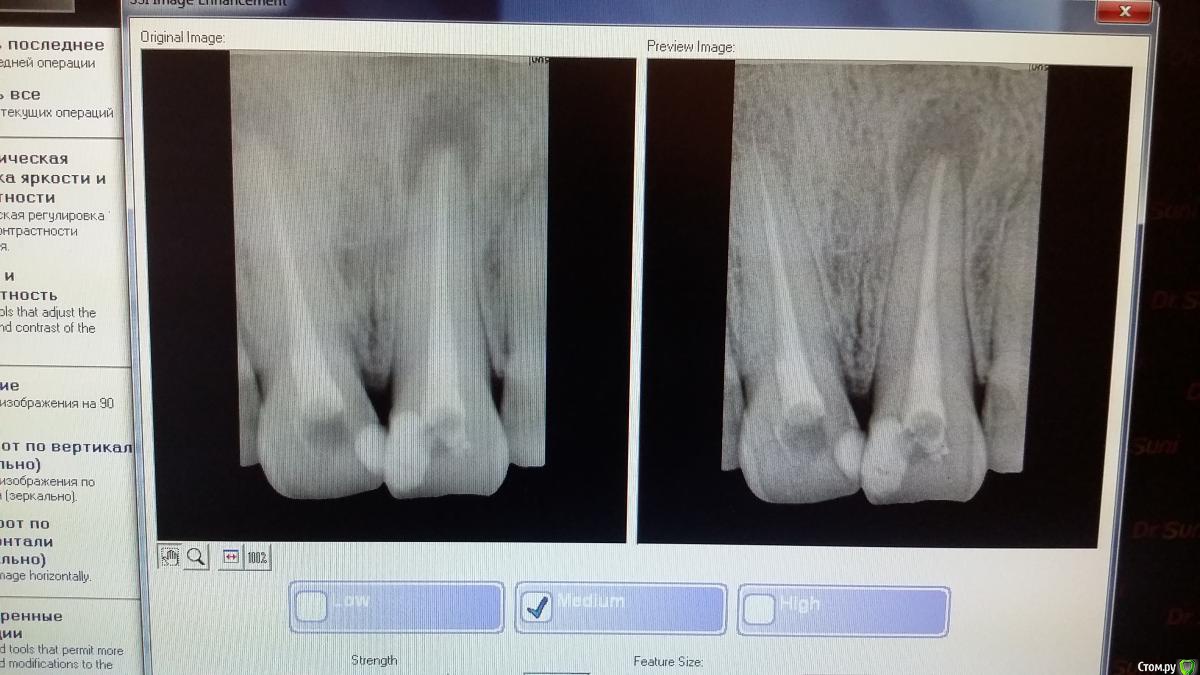

Recive Опубликовано 23 февраля, 2015 Автор Поделиться Опубликовано 23 февраля, 2015 Запломбировалммо +антеперь когда делать контрольный рентген? 2 Ссылка на комментарий

Гарриевич Опубликовано 23 февраля, 2015 Поделиться Опубликовано 23 февраля, 2015 через 6 месяцев Ссылка на комментарий